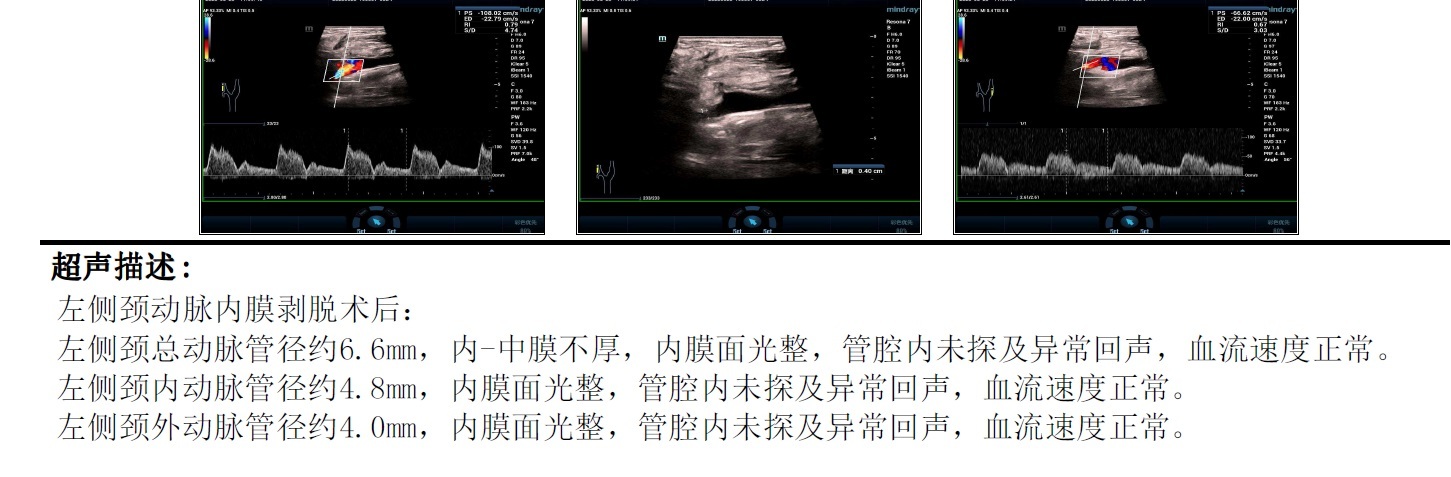

颈动脉内膜剥脱术